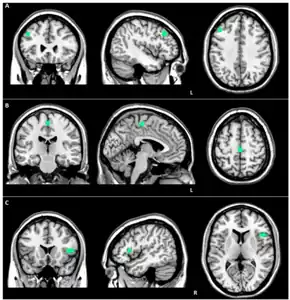

Brain MRI of a female of 65 years with frontotemporal dementia. Cortical and white matter atrophy of the frontal lobes is clear in all images.

a) Reduced EN connectivity in left middle frontal gyrus (FTD-GRN-) B) Reduced ventral SN connectivity in left medial frontal gyrus (GRN+) c) Reduced dorsal SN connectivity in right precentral gyrus (FTD-GRN+)